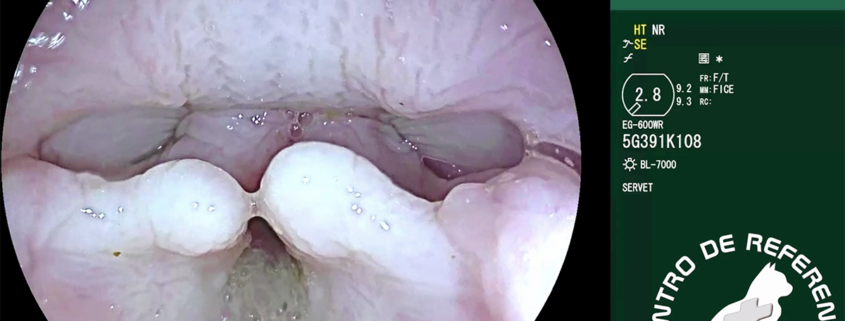

Colapso laríngeo síndrome braquiocefálico